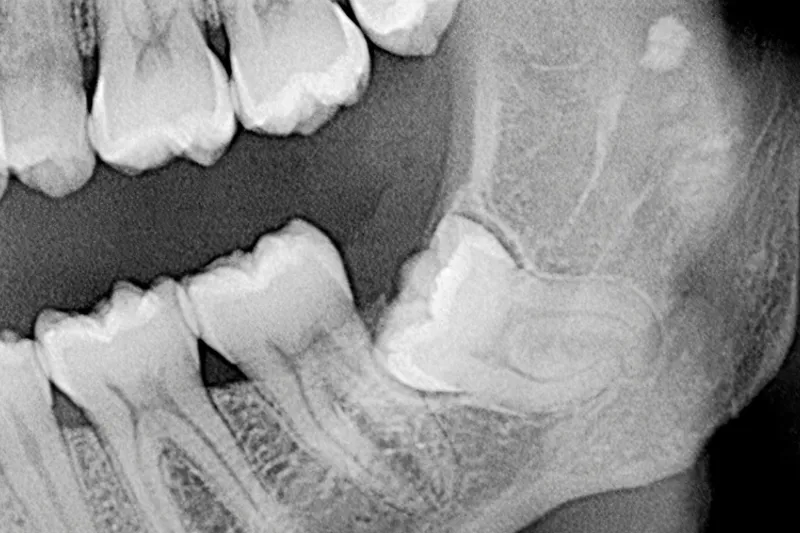

Radiologisk undersøgelse før kirurgisk fjernelse af mandiblens tredjemolar

Det er lege artis at foretage en røntgenundersøgelse forud for kirurgisk fjernelse af mandiblens tredjemolar (M3 inf.), og intraoral periapikal eller panoramaoptagelse anses for førstevalg, mens Cone Beam Computed Tomografi (CBCT) kan anvendes i særlige patienttilfælde, hvor der foreligger et ønske om en mere detaljeret radiologisk undersøgelse af relation mellem canalis mandibulae og rodkomplekset af M3 inf. samt eventuelt omkringliggende sygdom. Imidlertid er det vist, at radiologiske fund på CBCT hverken ændrer på behandlingen af M3 inf. eller på patientens postoperative forløb, herunder forekomsten af neurosensoriske forstyrrelser sv.t. n. alveolaris inferior (NAI). Derudover er det vanskeligt at identificere, hvilke radiologiske tegn der kan benyttes som prædiktorer for en neurosensorisk forstyrrelse sv.t. NAI. De klassiske syv panoramategn er således ikke længere valide. Nyere forskningsresultater på et højere evidensniveau har vist, at tilfælde, hvor M3 inf.’s rødder strækker sig kaudalt for den nedre begrænsning af c. mandibulae, er forbundet med en øget forekomst af permanent neurosensorisk forstyrrelse. Den generelle anbefaling vedrørende radiologisk undersøgelse før kirurgisk fjernelse af M3 inf. er derfor, at 2D radiologisk undersøgelse er tilstrækkeligt i hovedparten af de patienttilfælde, hvor M3 inf. skal fjernes.

A radiographic examination is required before removal of mandibular third molars (M3 inf.). An intraoral or panoramic examination should always be the first choice, and cone beam computed tomography (CBCT) can be considered in special patient cases, where the relation between the mandibular canal and M3 inf. needs to be assessed in a more detailed radiographic examination and in case of suspected pathology related to M3 inf. For mandibular third molars, it has been shown that CBCT changes neither the treatment plan nor the post-operative outcome for the patient including the incidence of neurosensory disturbances of the inferior alveolar nerve. Moreover, it is difficult to identify radiographic risk factors for a neurosensory disturbance of the inferior alveolar nerve. The seven classic signs in panoramic images are no longer considered valid. Recent research on a higher level of evidence has found that if the root of third molar extends below the lower border of the mandibular canal, there is an increased risk of permanent neurosensory disturbances. Overall, a 2D image is sufficient in the majority of cases before surgical intervention.